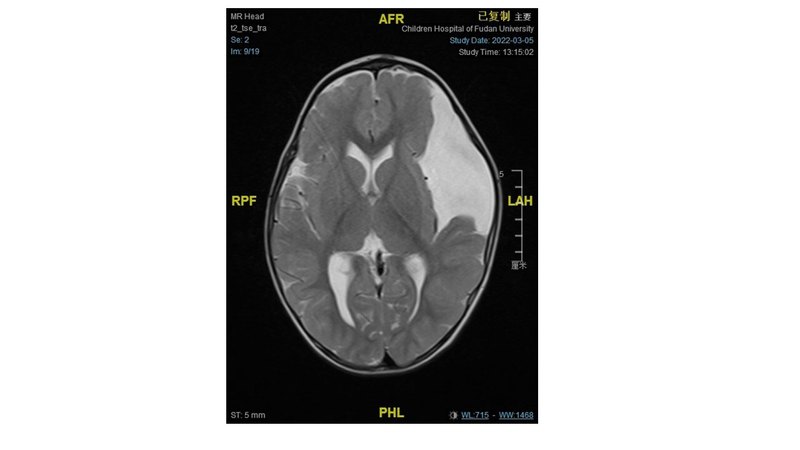

顱內(nèi)蛛網(wǎng)膜囊腫是一種位于大腦蛛網(wǎng)膜下腔的液體充滿的良性囊腫。這種囊腫可以是先天性的,也可能是后天性的,如頭部受傷或其他疾病后形成。以下是顱內(nèi)蛛網(wǎng)膜囊腫的常見分類和部位:按部位分類蛛網(wǎng)膜囊腫可以發(fā)生在大腦的任何位置,但有些部位更為常見:中顱窩囊腫:位于大腦的中間部分,是最常見的蛛網(wǎng)膜囊腫類型。顳葉囊腫:位于大腦顳葉內(nèi),可能會(huì)影響語言和記憶。額葉囊腫:位于大腦額葉區(qū)域,可能影響個(gè)性和行為。枕葉囊腫:位于大腦的后部,可能影響視覺。小腦囊腫:位于大腦的后下方,影響協(xié)調(diào)和平衡。橋腦囊腫:位于腦干附近,可能影響許多生命支持功能。腦室旁囊腫:位于大腦腦室周圍,可能影響腦脊液的流動(dòng)。蛛網(wǎng)膜囊腫的癥狀和治療需求可以根據(jù)其大小、位置以及是否引起大腦結(jié)構(gòu)的壓迫而有很大的差異。輕微的或無癥狀的囊腫可能不需要治療,而較大或有癥狀的囊腫可能需要通過手術(shù)來治療。顱內(nèi)蛛網(wǎng)膜囊腫的手術(shù)治療方式主要旨在減少囊腫對周圍腦組織的壓迫,恢復(fù)腦脊液的正常流動(dòng),以及防止囊腫再次積聚。以下是幾種常見的手術(shù)方法:1.?開顱切除術(shù):這是一種傳統(tǒng)的手術(shù)方法,通過在頭骨上開一個(gè)窗口來直接探查囊腫。然后,外科醫(yī)生會(huì)盡可能地切除囊腫壁和囊腫內(nèi)容物,目的是徹底移除囊腫,減輕對周圍腦組織的壓迫。適用情況:主要用于那些位置表淺的大型囊腫。2.?腦室囊腫-腦室造口術(shù):這種方法通過在囊腫和鄰近腦室之間創(chuàng)建一個(gè)開口,使囊腫內(nèi)的液體可以流入腦室系統(tǒng),并通過腦脊液正常的循環(huán)路徑被吸收。適用情況:適用于靠近腦室系統(tǒng)的囊腫。3.?囊腫腹腔分流術(shù):這種手術(shù)涉及將一個(gè)分流管(一種細(xì)長的管子)從囊腫引流到腹腔中,從而持續(xù)地將囊腫內(nèi)的腦脊液引流到身體的其他部位進(jìn)行吸收。適用情況:適用于囊腫重新積聚的高風(fēng)險(xiǎn)病例或其他手術(shù)方法不適用的情況。4.?內(nèi)鏡下囊腫造口術(shù):這是一種微創(chuàng)手術(shù)方法(目前最常用的手術(shù)方法),通過使用內(nèi)鏡設(shè)備,在囊腫壁上大一個(gè)或多個(gè)小孔,以促進(jìn)液體排出和減少囊腫體積。適用情況:適用于位于腦室附近或與腦室系統(tǒng)有潛在通路的囊腫。兒童顱內(nèi)蛛網(wǎng)膜囊腫的手術(shù)指征主要是基于囊腫導(dǎo)致的癥狀、囊腫的增長速度以及囊腫對周圍腦組織的影響。手術(shù)的主要目的是為大腦發(fā)育創(chuàng)造空間,改善由囊腫壓迫引起的癥狀,從而提高患兒的生活質(zhì)量。以下是幾個(gè)關(guān)鍵的手術(shù)指征:1.?癥狀性囊腫:囊腫引起的癥狀通常是進(jìn)行手術(shù)治療的主要指征。這些癥狀可能包括:頭痛、癲癇發(fā)作、神經(jīng)功能損害(如運(yùn)動(dòng)或感覺障礙)、認(rèn)知或行為問題、視力問題2.?囊腫大小增長:通過影像學(xué)監(jiān)測發(fā)現(xiàn)囊腫體積明顯增大,尤其是伴隨癥狀加重的情況,通常需要手術(shù)干預(yù)。3.?對腦部結(jié)構(gòu)的影響:如果囊腫導(dǎo)致周圍腦組織的顯著位移或?qū)δX脊液流動(dòng)造成阻塞(比如引起腦室擴(kuò)大),即使癥狀不明顯,也可能需要考慮手術(shù)。4.?潛在并發(fā)癥:對于可能導(dǎo)致嚴(yán)重并發(fā)癥的囊腫,如囊腫破裂或感染,即便癥狀不嚴(yán)重,也可能需要手術(shù)干預(yù)。手術(shù)目的:1.減輕壓迫癥狀:通過減少囊腫體積或去除囊腫,減輕其對周圍腦組織的壓迫,從而改善或消除癥狀。2.促進(jìn)正常腦發(fā)育:通過消除囊腫引起的異常壓力,為大腦提供更健康的發(fā)育環(huán)境。3.恢復(fù)腦脊液流動(dòng):如果囊腫阻礙了腦脊液的正常流動(dòng),手術(shù)可以幫助恢復(fù)其流動(dòng),防止因腦脊液積聚而導(dǎo)致的并發(fā)癥,如腦室內(nèi)積水(腦積水)。案例